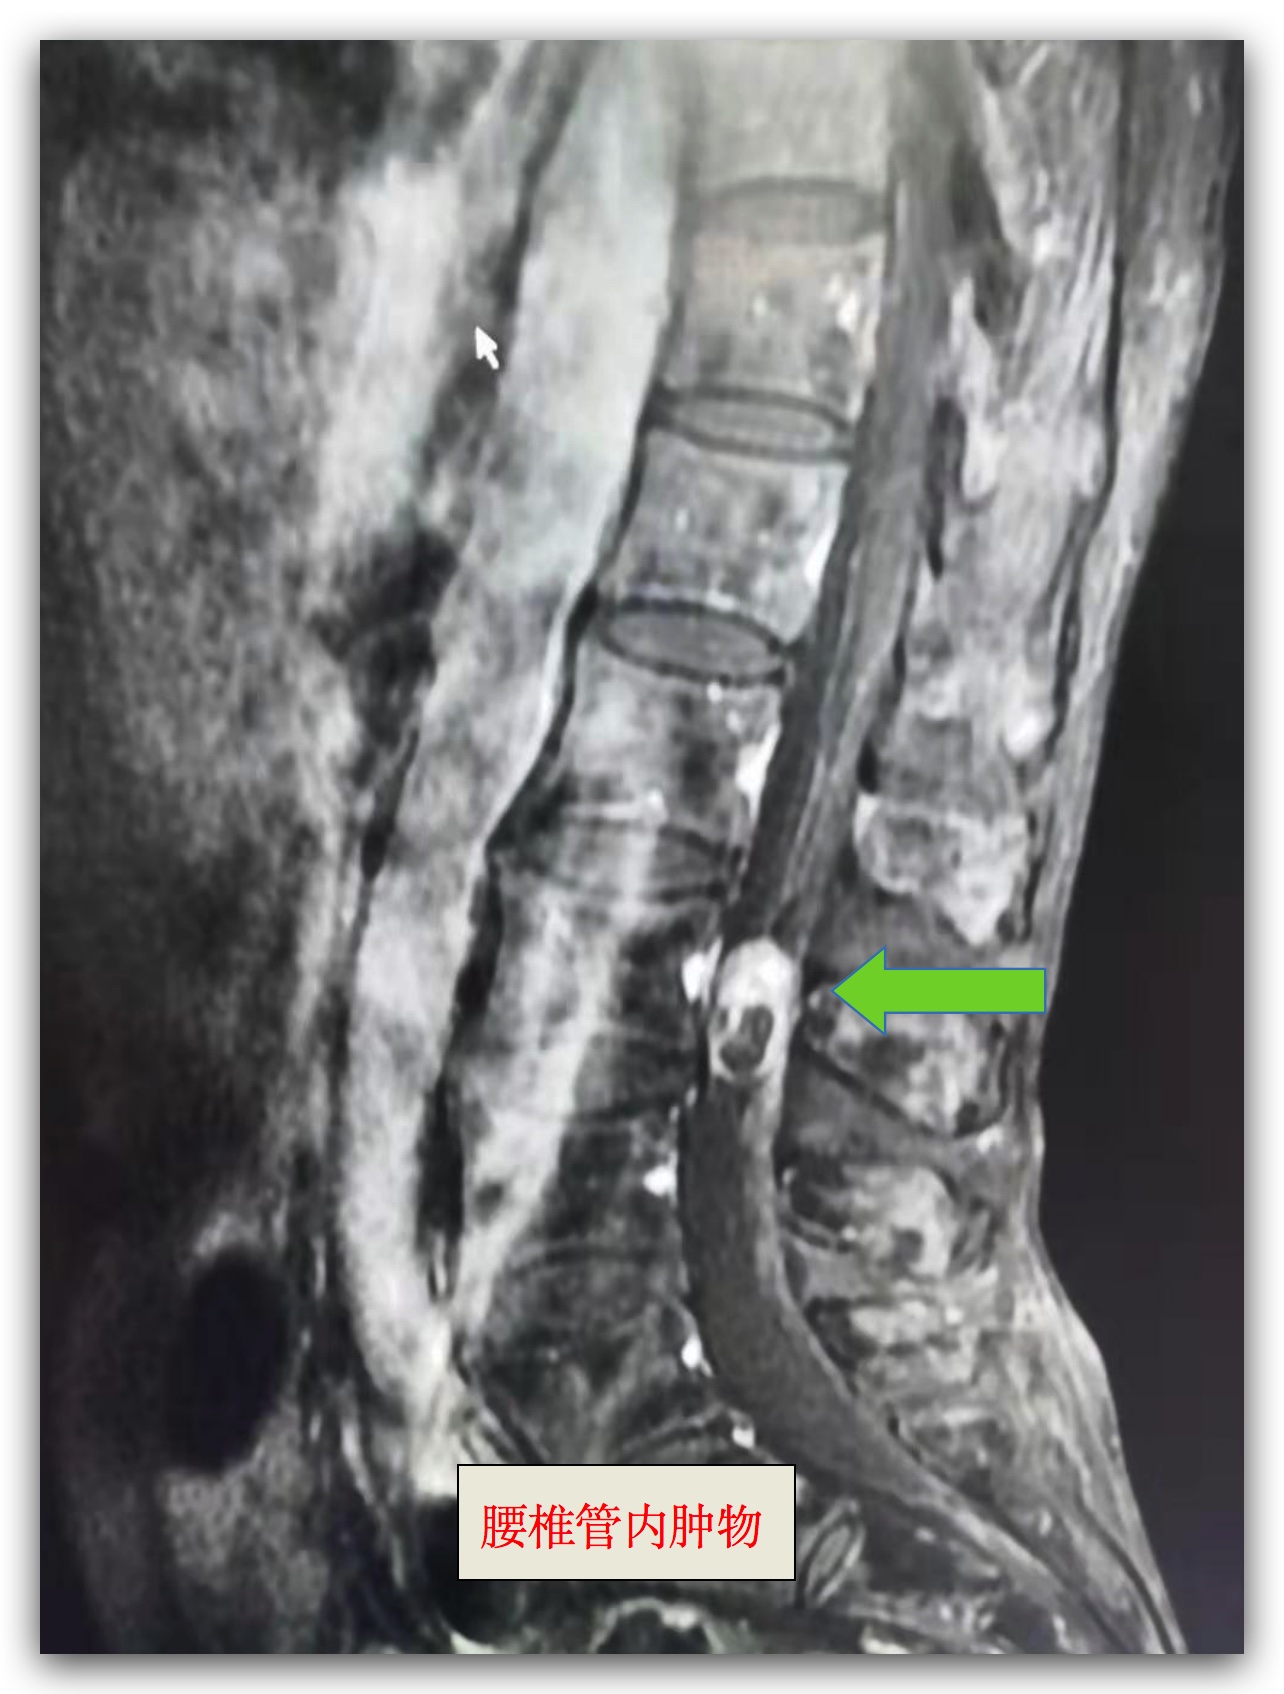

案例二:

腰椎管内占位病变

患者陈女士,68岁,腰痛及左下肢疼痛3个月,近期疼痛明显加重,难以忍受, 严重影响生活质量,院外多次就诊,无明显效果,为求进一步诊断及治疗,于6月17号收入我科,经过系统查体及相关辅助检查,明确诊断示:腰椎管内占位病变,考虑神经源性肿瘤,科主任卜祥鹏、副主任医师李秀春积极讨论治疗方案,于6月22日施行腰椎板切开、椎管内肿瘤切除、RSS内固定术,手术顺利完成,术后疼痛即明显缓解,患者经过12天的药物及肢体功能锻炼,现已康复出院。